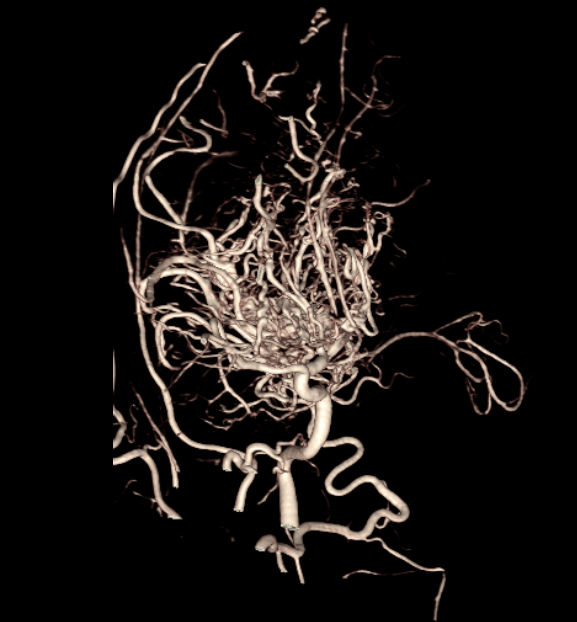

入院后,郑州市中心医院神经外科主任吕国伟详细查阅妍妍的检查资料,为她安排了脑灌注(PWI)和脑血管造影(DSA)等术前评估。结果显示:双侧额颞顶叶脑血流达峰时间及平均通过时间均延长,脑血流显著减低,低灌注区体积达81.3ml(红色区域为脑灌注不足部分)。脑血管造影进一步证实:双侧大脑中动脉、大脑前动脉闭塞,大量烟雾状血管生成。

术前脑血管造影显示,妍妍右侧脑膜中动脉已起到颅内供血代偿作用。这意味着,术中打开颅骨时,必须小心保留骨板下的这支“生命血管”,否则可能引发术后缺血并发症。凭借丰富的手术经验和术前精密规划,吕国伟在高倍荧光显微镜下娴熟操作:分离供体血管、小骨窗开颅、保护脑膜中动脉、打开蛛网膜下腔……术中荧光造影显示,搭桥血管非常通畅。